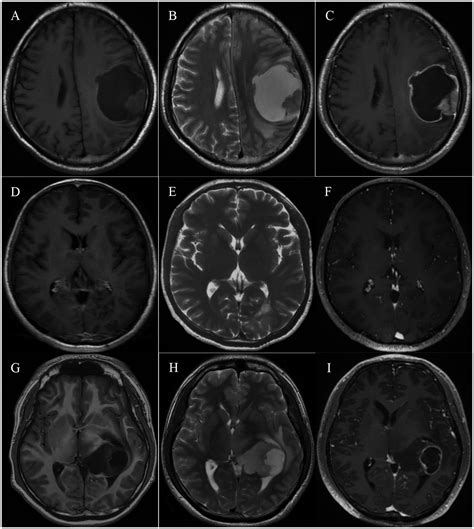

The journey toward a formal diagnosis usually begins with a neurological examination followed by advanced imaging. Physicians rely on several diagnostic tools to map the tumor’s size, location, and relationship to vital brain structures. Magnetic Resonance Imaging (MRI) with contrast remains the gold standard for visualizing these growths. In many cases, specialized sequences such as spectroscopy or perfusion imaging are used to differentiate between tumor tissue and postoperative changes.

• high grade glioma MRI